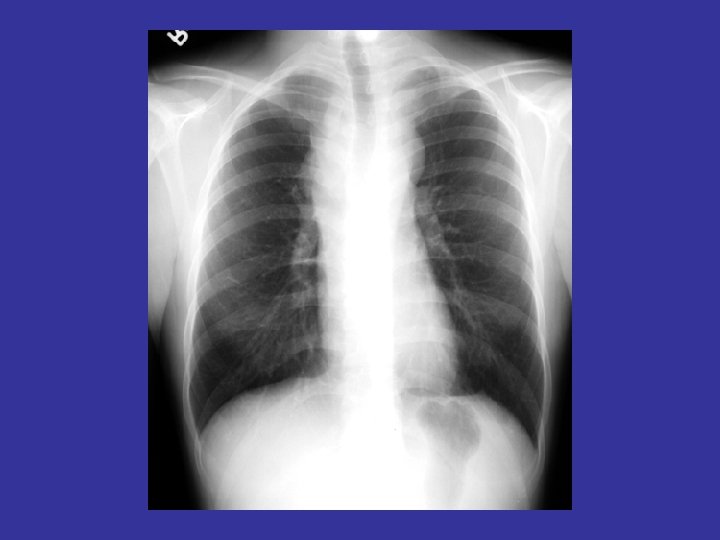

How to read a chest x ray ? • 1 - chest wall, bones

How to read a chest x ray ? • 1 - chest wall, bones and abdomen * bones; lesions or fractures * soft tissue ; mastectomy or soft tissue tumors • 2 - heart and mediastinum * trachea ; position & caliber * hila : lymphadenopathy * mediastinum contour : ? mass * heart : cardiac configuration • 3 - lungs opacity or lucency